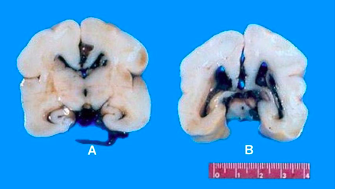

What is this diagnosis of a premature baby? [1]

Interventricular haemorrhage

If a baby suffers from these symptoms, they are most likely to be suffering from:

Toxoplama gondii

Intracranial calcification

Hydrocephalus

Chorioretinitis